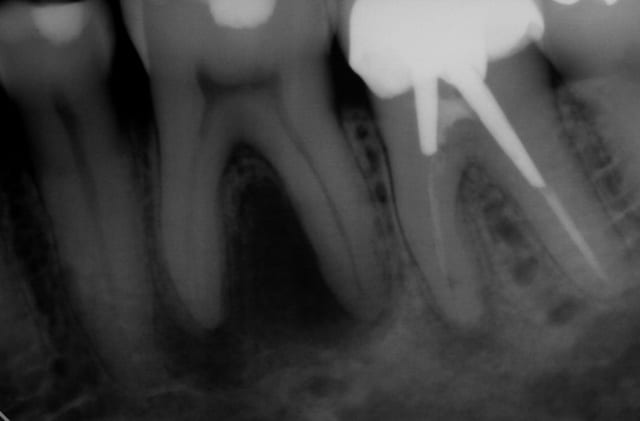

Bonsoir je poste ces 2 radios pour vous demander 2 avis.

Un avis d'ordre général. Sur la 1ère radio bite wing.

Le patient n'a pas de douleurs. On voit une rétraction pulpaire signifiant un mécanisme de défense face à la carie.

Je voulais savoir si vous tentiez systématiquement le coiffage pulpaire direct à la biodentine. J'ai évidemment fait une effraction pulpaire lors du soin de la carie. Pourtant j'ai essayé de ne pas la faire ...

Quel est le pourcentage de chance de ne pas avoir de pulpite ou nécrose dans le cas d'une dent asymptomatique ou voire même symptomatique calmée au paracétamol?

Le coiffage pulpaire peut être tenté seulement si certains critères sont respectés : pulpe asymptomatique, ouverture sous digue, reconstitution composite fiable possible (autrement dit petite cavité de carie). Ici je ne pense pas que ces critères soient réunis.

Si tu peux te permettre le coiffage de la prémolaire à la biodentine, c'est une excellente indication. Il faut remplir la cavité (bien nettoyée) et revoir l'obturation dans un second temps, pour mettre un composite en surface puisque la biodentine n'est pas très solide.